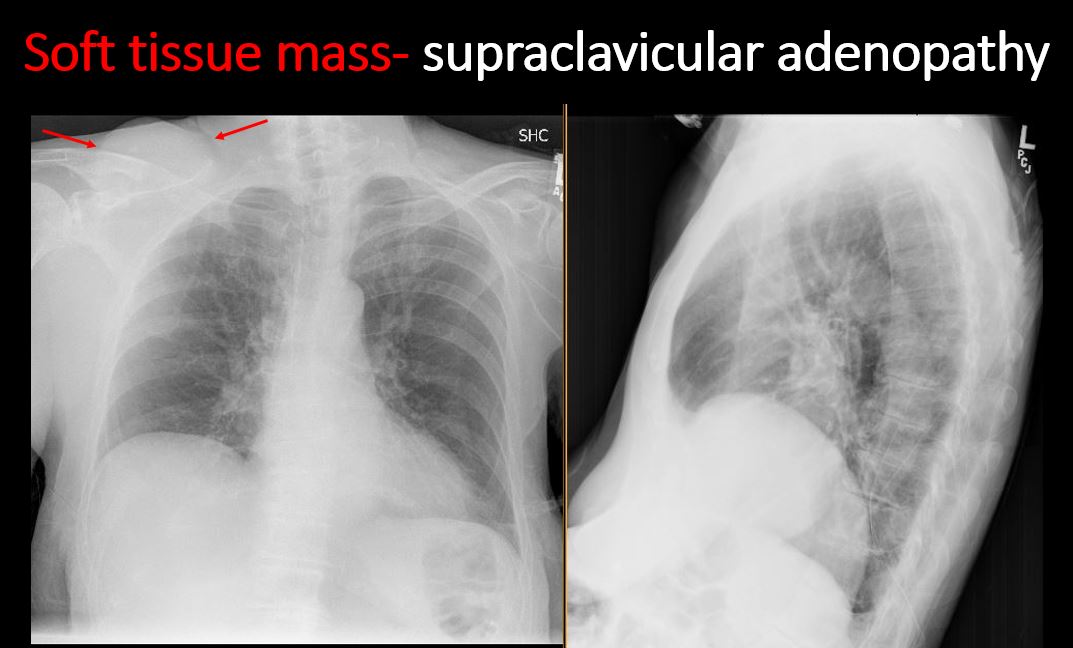

Section 1 Submit Findings Case322 Findings Technique The exam is expiratory, rotated, over or under penetrated, or limited by overlying structures or soft tissues, body habitus, patient positioning, or motion. Yes No Support Devices There is a vascular line or lines present in an abnormal location or otherwise abnormal. Yes No There are other devices such as a chest tube or pleural drain, feeding, NG, or gastrostomy tube, LVAD or pacemaker, vascular stents, cardiac valves, anesthesia catheter, VP shunt, neurostimulator, or other drains or tubes present that are in an abnormal position or are otherwise abnormal. Yes No Cardiomediastinum The superior mediastinum is abnormally widened considering the technique. Yes No There is abnormal shift of the mediastinum. Yes No There is a mass or other abnormal density in or overlying the mediastinum. Yes No There is an abnormality in the retrosternal, retrotracheal, or retrocardiac space on the lateral view. Yes No There is abnormal tracheal deviation or narrowing on the frontal and/or lateral view. Yes No There is pneumomediastinum and/or pneumopericardium. Yes No There is enlargement of the cardiac silhouette. Yes No The heart borders are abnormal. Yes No The right paratracheal stripe is thickened or enlarged. Yes No The azygoesophageal recess is displaced or otherwise obscured. Yes No Vasculature and Hila The aorta is dilated, tortuous, ectatic, calcified, or there is a focal contour abnormality. Yes No The central pulmonary arteries or hila are enlarged. Yes No The aorto-pulmonary window is convex or obscured by a mass, adenopathy, or vasculature. Yes No There is cephalization or haziness of the pulmonary vessels or congestion of the central pulmonary vasculature. Yes No Lungs The lungs are hyperinflated or underinflated generally or segmentally. Yes No There is focal, multifocal, or diffuse airspace disease, mass, opacity, or nodularity. Yes No There is focal or diffuse interstitial disease. Yes No There is focal or lobar atelectasis or total collapse of the lung. Yes No There is cavitary or cystic disease with or without air fluid levels or soft tissue nodularity. Yes No The position of the major and minor fissures is abnormal. Yes No The right or left hemidiaphragm is focally or diffusely obscured on the frontal and/or lateral view. Yes No There is elevation, depression, or contour abnormality of the right or left hemidiaphragm. Yes No Pleura There is focal or diffuse abnormality of the pleura or chest wall. Yes No There is a pleural effusion, blunting of the costophrenic angle, or posterior sulci. Yes No There is focal fluid in the fissures. Yes No There is asymmetric pleural thickening or capping of the apices. Yes No There is a pneumothorax, hydro/pneumothorax, or hemo/pneumothorax. Yes No Bones, Soft Tissues, Upper Abdomen The ribs, clavicles, shoulder, spine, or other visualized bones are abnormal. Yes No There is free air beneath the diaphragm. Yes No The bowel or organs of the upper abdomen are abnormal. Yes No There is subcutaneous emphysema, focal or diffuse soft tissue abnormality, radiopaque foreign body, or post-surgical change or hardware. Yes No